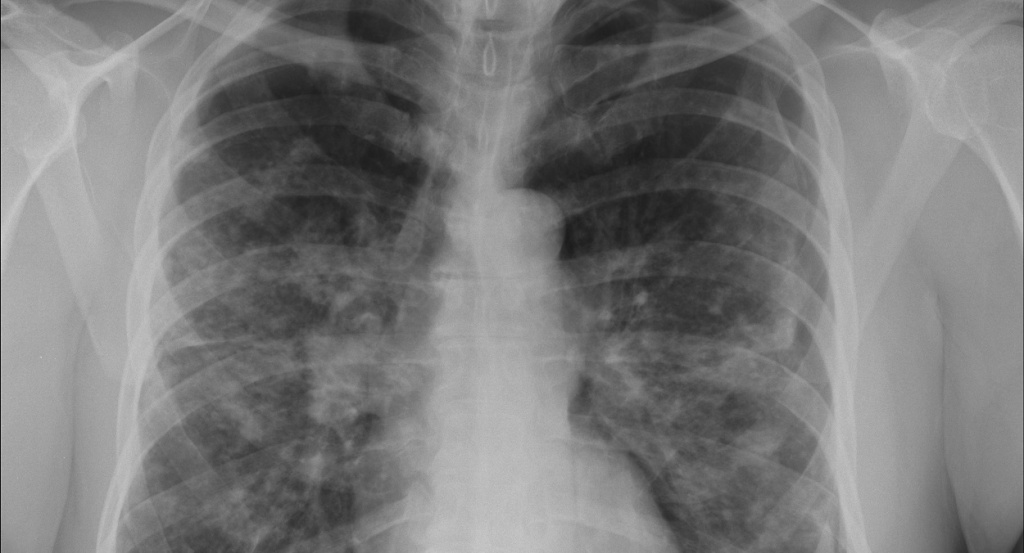

• Рентген легких.

• КТ  и  МРТ.